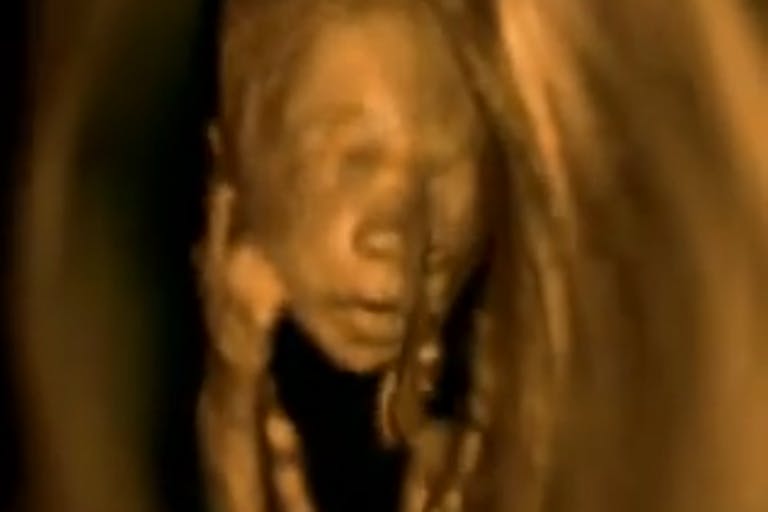

Remarkable 3-D ultrasound video shows humanity of preborn children

This video from a medical diagnostic center in Kiev, Ukraine, shows both early and late fetal development and has been viewed more than 1.4 million times on Facebook. The text states, “What are the babies inside mom. Remarkable video! The video cut through a 3 D Ultrasound.”

These are not clumps of cells. They are human beings exhibiting human behavior in the womb: